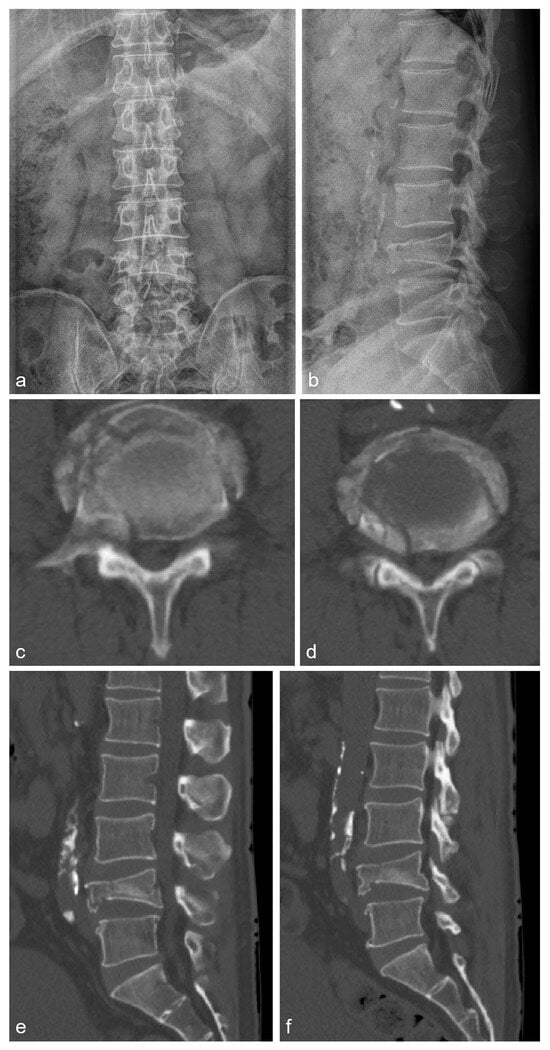

2.1. Case 1

2.2. Case 2